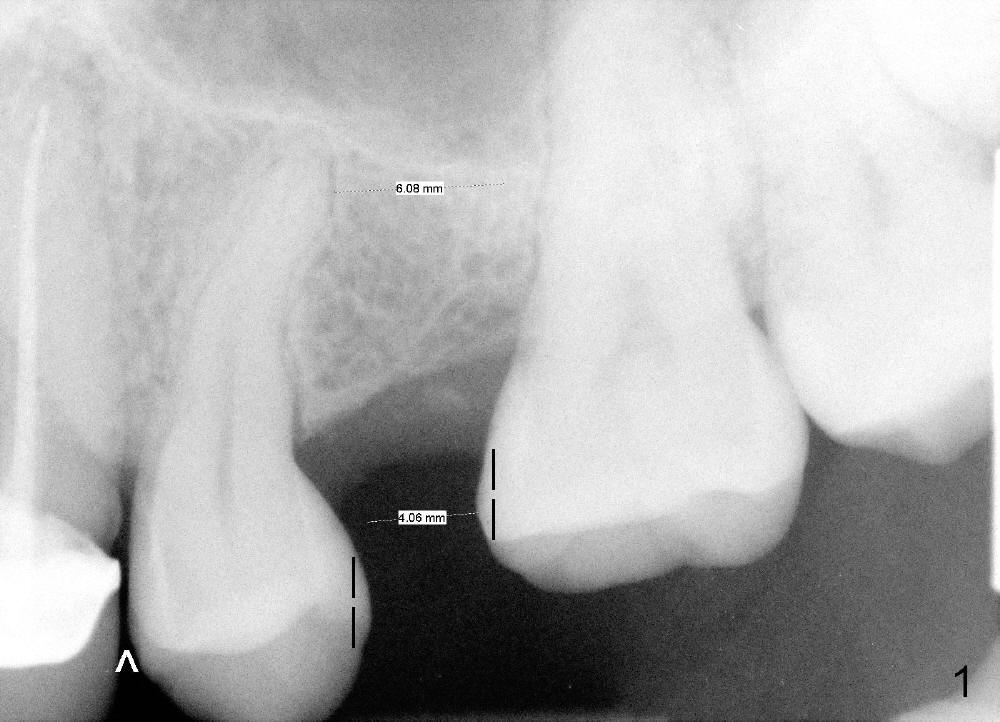

A 39-year-old lady is a dental phobic and finally agrees to restore long-termed missing upper left 2nd premolar (Fig.1). The adjoining teeth tilt toward the edentulous space. To place a 3.8x8 mm submerged implant (Fig.2, CBCT coronal section), enameloplasty is done (compare Fig.1 dashed lines with Fig.3 <). Since the density of the cancellous bone (<100 Hounsfield units (HU)) is much lower than that of the crest (300-400 HU) (Fig.2' <), osteotomy is initiated by 2 mm pilot drill (Fig.3 P) and finished by osteotomes (2 and 3 mm), bone expanders (2.6 mm (Fig.4) and 3.2 mm) and 3.8 mm tap drill. The implant is placed as planned with insertion torque around 35 Ncm (Fig.5). The implant is further lifted into the sinus by 1 mm without bone graft following the last X-ray. A healing abutment (4.1x3) is placed (Fig.6 <).